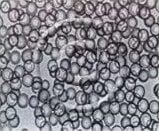

Figure 1. Yttrium 90 microspheres

Radioactive material gives off invisible rays which can cause harm and death to normal or cancerous cells. The most obvious example of radiation treatment used to treat cancer is in breast cancer. The rays are delivered from a machine onto the breast or the chest wall in an attempt to reduce the risk of recurrent breast cancer. In SIR therapy, the appropriate amount of radiation material, called yttrium-90 (y-90), is delivered in the form of microscopic spheres into the liver cancer via the hepatic artery. These radioactive microspheres (Figure 1), once deposited into the cancerous tumour, will emit the invisible rays and kill the cancer cells.